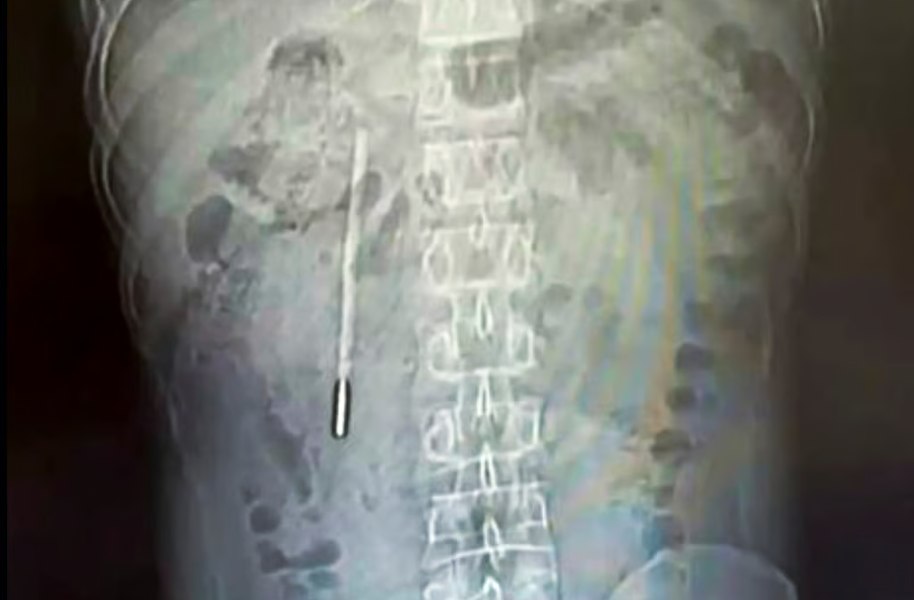

Un bărbat în vârstă de 32 de ani din China, care s-a prezentat la spital acuzând dureri abdominale, a avut un șoc când a aflat că un termometru cu mercur, pe care îl înghițise în copilărie, se afla încă în corpul său.

Ce au găsit medicii în stomacul unui bărbat: secretul păstrat 20 de ani